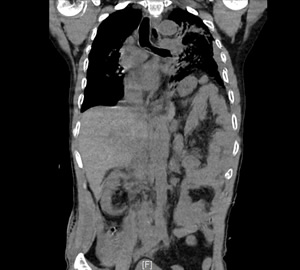

患者左下肺炎症、左侧胸腔积液、纵隔右移 患者部分肠管及胃疝到左侧胸腔